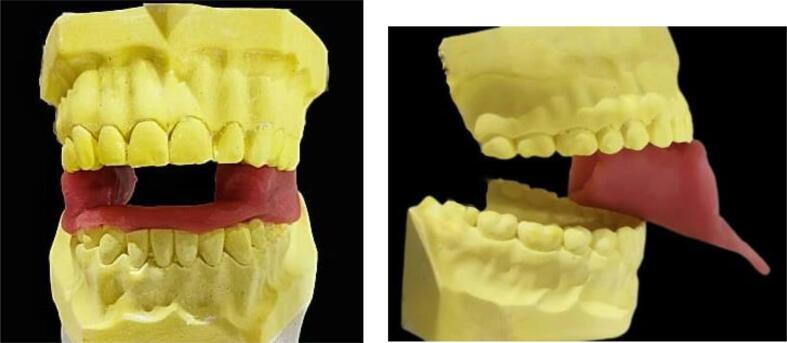

Radiation therapy (RT) is a common modality of treatment in patients with head and neck cancer, and can cause several oral complications. These mainly include radiomucitis, oral pain, hyposalivation, limitation of mouth opening, and osteoradionecrosis.There are different intraoral devices aimed at reducing these complications. It can be used in association with the therapy of RT. They are used to protect healthy tissues surrounding the site to be irradiated, carry the radiation source, move away from certain anatomical structures, position certain devices, and to allow tissue remodeling.The collaboration between the maxillofacial prosthodontist specialist and the radiotherapist is necessary for the design and realization of these devices which differ according to each clinical situation.This work aims to review and illustrate the different radiation devices used in combination with head and neck radiotherapy and introduce a new device design to protect and remove non-radiation-targeted structures.

放射治疗(RT)是头颈癌患者常用的治疗方式,可引发多种口腔并发症。这些并发症主要包括放射性粘膜炎、口腔疼痛、唾液分泌减少、张口受限和放射性骨坏死。有不同的口腔内装置旨在减少这些并发症,可与放射治疗联合使用。它们用于保护待照射部位周围的健康组织、携带放射源、远离某些解剖结构、定位某些装置以及促进组织重塑。颌面修复专家与放射治疗师之间的合作对于设计和制作这些因临床情况而异的装置至关重要。本研究旨在回顾和阐述与头颈放疗联合使用的不同放射装置,并介绍一种用于保护和移开非放射靶结构的新装置设计。